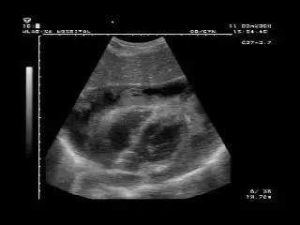

3、超聲心動圖:M型超聲在心前壁之間和心後壁之後均見有液性暗區,即當心包膜和心外膜之間最大舒張期暗區(10毫米時,則積液為小量;如在10-19毫米之間則為中等量;如大於20毫米,則為大量)。